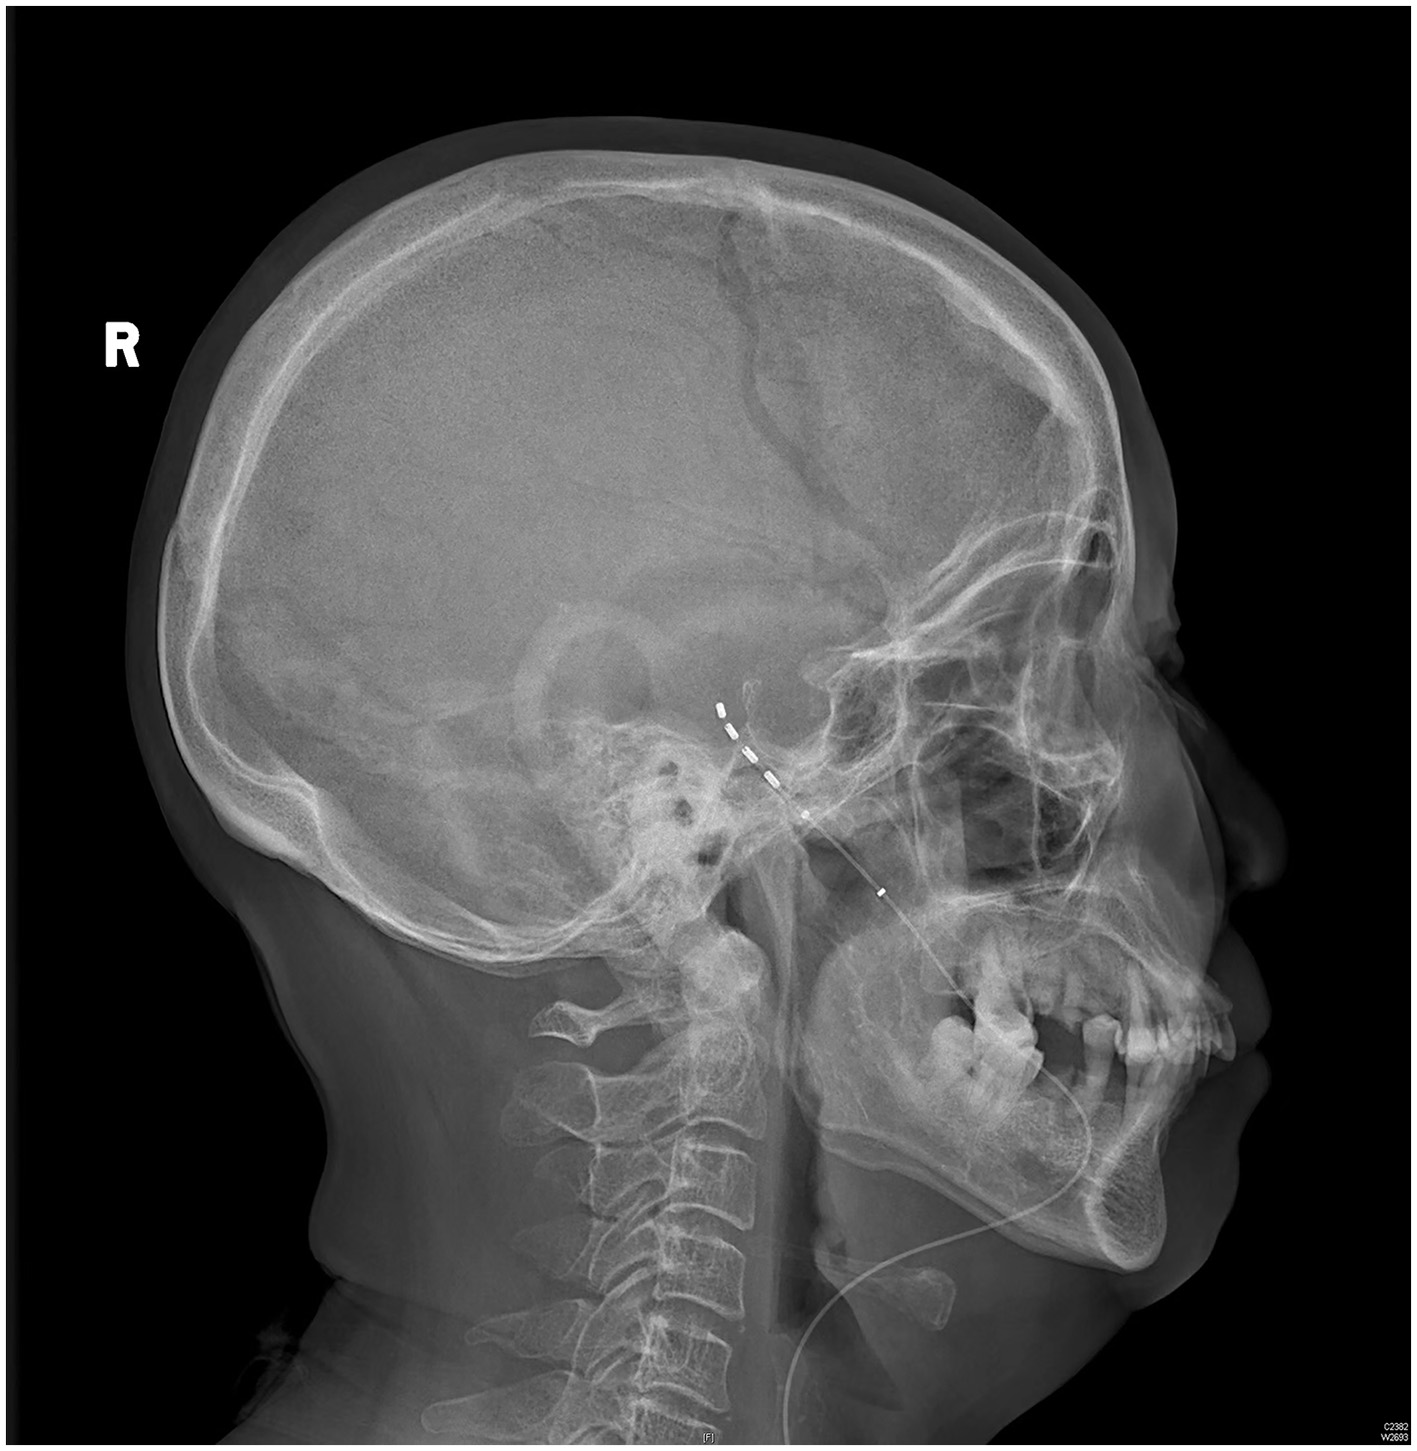

The patient rated her facial pain on the VAS as 3/10 with paresthesia sensation on the left side of her face the day after implantation. The pain reduced to 1/10 on the VAS 3 days after implantation. After the 14-day stimulation, the patient underwent a skull-base x-ray scan (Figures 3, 4), which revealed that the quadripolar electrode had bent over the Gasserian ganglion without dislocation. Furthermore, after the patient rated that satisfactory pain relief was achieved with pregabalin, the dosage was reduced to 75 mg at night and the electrode was pulled out. SDS, SAS, and SF-12 were evaluated again before discharging the patient. The results indicated a significant improvement in pain as compared to before surgery. VAS, oral medication, and complications were followed up through telephone interviews at 1, 3, 6, and 12 months by the pain physician (Table 1). At the 12-month follow-up after surgery, the patient's VAS score was 4/10, and the patient was taking 75 mg of pregabalin orally per night. Although a small increase was noted in the VAS score at the 12-month follow-up after surgery compared to the VAS score at the time of discharge, the patient's trigeminal pain decreased by over 50% compared to the VAS score at the time of admission, which indicated that stable and satisfactory pain relief was achieved through temporary GGS.

Figure 4

A skull-base x-ray of the lateral view.